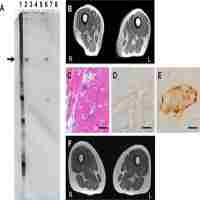

| Abstract | Patients suffering from recurrent tonsillitis (RT), hyperplastic tonsillitis (HT) or idiopathic tonsillar hyperplasia (ITH) were compared in immunological studies with subjects showing clinically normal palatine tonsils. Serum concentrations of immunoglobulins, particularly IgG, were increased in association with tonsillitis. Conversely, the number of IgG-, IgA- and IgM-producing immunocytes was reduced per tonsillar tissue unit. The density of such cells was decreased in the germinal centres of the lymphoid follicles, in the extrafollicular areas and in the reticular parts of the crypt epithelium. However, only small changes in immunocyte class ratios were observed, excepting a significantly raised proportion of IgD-producing cells. The immunohistochemical results indicated a defect in the tonsillar immunological function associated with disease, perhaps as a result of inadequate stimulatory signals for local maturation of B-cell clones. An influence of low age on this result in the HT and ITH groups could not be excluded. In the RT group there was a significant negative correlation between the tonsillar density of IgA-producing cells and the rate of synthesis of serum IgA. This may indicate that compensatory mechanisms are reflected in inversely related levels of local and systemic IgA synthesis. |